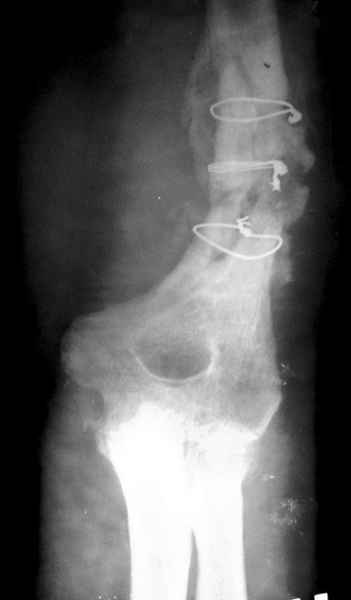

Второй случай, также после множественных операций:

пластина, аппарат, серкляж и парез нерва.

Также ревизия, из-за низкого состояния доступ был сделан через

остеотомию локтевого отростка.

Ложный сустав фиксирован двумя локинг плейт с аутокостной пластикой,

также через два месяца увидели признаки консолидации.

Движение в суставе разрешили в две недели.

Вложение не в текстовом формате было извлечено…

Имя     : 2 mukh lat.jpg

Тип     : image/jpeg

Размер  : 22657 байтов

Описание: отсутствует

Url     : http://weborto.net:8080/pipermail/ortho/attachments/20080223/b621f987/attachment-0007.jpg